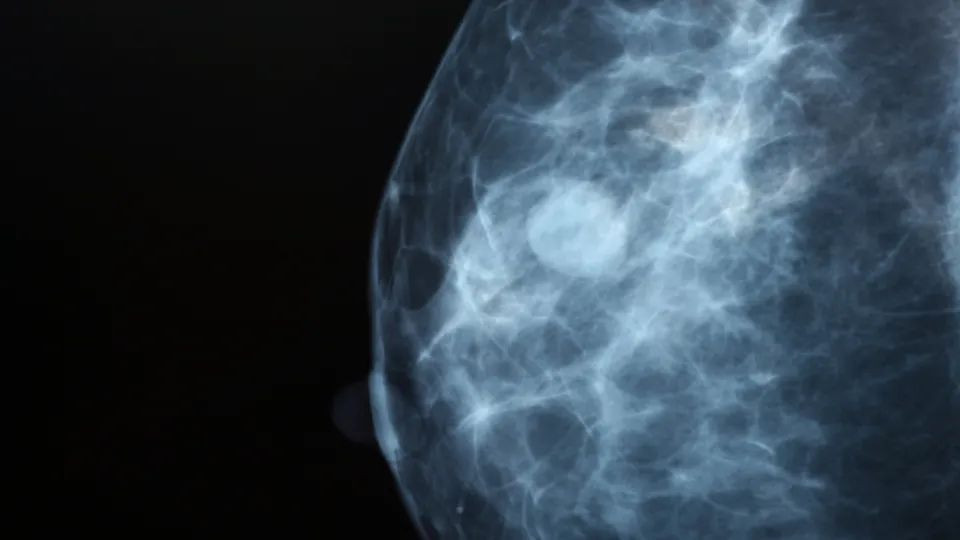

Η μελέτη συνέκρινε δύο ομάδες: μία που υποβλήθηκε σε τυπική μαστογραφία με διπλή ανάγνωση από δύο ακτινολόγους και μία όπου η εξέταση υποστηρίχθηκε από AI. Στην ομάδα της τεχνητής νοημοσύνης, το σύστημα ανέλυε τις εικόνες και διαχώριζε τα περιστατικά. Τα χαμηλού κινδύνου περιστατικά ελέγχονταν μόνο από έναν ακτινολόγο, ενώ τα ύποπτα παραπέμπονταν για διπλή ανάγνωση.

Παράλληλα, καταρρίφθηκε ένας από τους βασικούς φόβους που συνοδεύουν την εισαγωγή νέων τεχνολογιών: η αύξηση των ψευδώς θετικών αποτελεσμάτων. Τα ποσοστά των γυναικών που κλήθηκαν λανθασμένα για επανέλεγχο παρέμειναν στα ίδια επίπεδα με την παραδοσιακή μέθοδο (1,5% στην ομάδα AI έναντι 1,4% στην ομάδα ελέγχου), αποδεικνύοντας την υψηλή ακρίβεια του αλγορίθμου.